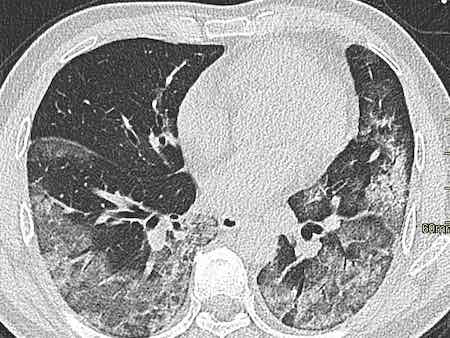

Covid CT Pattern

These are the latest Covid CT Pattern images from around the world.